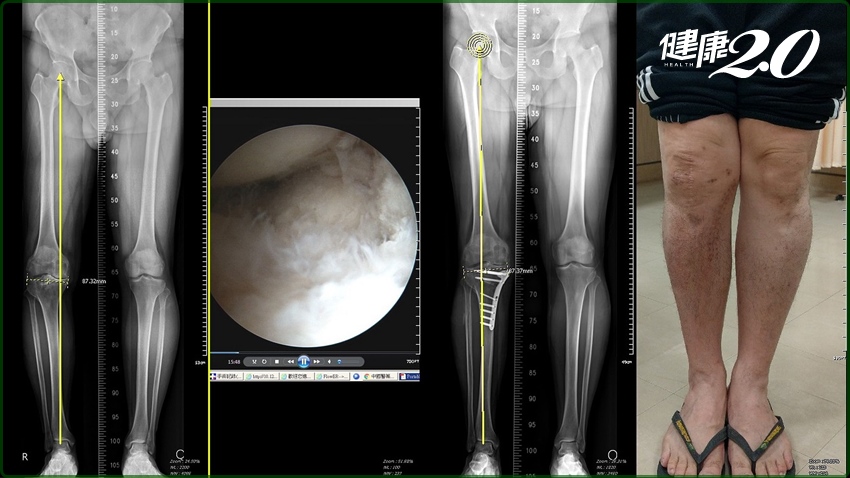

▲膝蓋損磨退化,截骨矯正術有機會不用換關節。

此外,對於車禍受傷造成脛骨骨折後遺存變形,導致膝蓋呈現內翻的情況,也可採用截骨矯正術。45歲的陳先生在20多歲時因為車禍脛骨骨折,雖然行動不便,疼痛偶爾發作尚可忍受,但最近3年來疼痛加劇,無法長時間行走或站立,採用新手術後,不僅成功保住膝蓋,膝蓋活動也變敏捷。

▲車禍造成膝蓋疼痛的陳先生,經過新保膝術後,行動已恢復往日的敏捷。